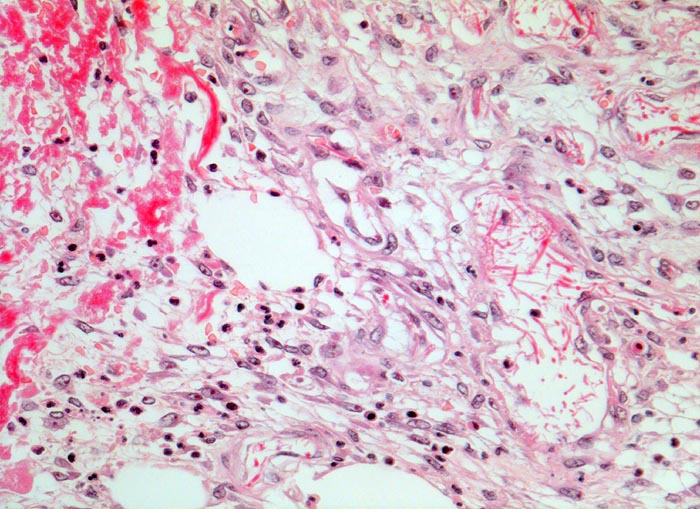

• Zweite Phase: Aufbau von Granulationsgewebe (= zell- und gefäßreiches Bindegewebe). Die Kapillarisierung (Neovaskularisation) durch Einsprossen von Blutgefäßen (Gefäßbäumchen sind als hellrote, glänzende Körnchen im Wundgrund sichtbar) sorgt für ausreichende Ernährung des Gewebes. Die Kollagensynthese durch eingewanderte Fibroblasten benötigt Vitamin C und Sauerstoff.

Morphologische Merkmale:

• Schlitzförmiger, bis in die Subkutis reichender Hautdefekt.

• Neugebildete Epidermis bedeckt im oberen intradermalen Anteil des Wundspaltes teilweise den Gewebsdefekt.

• Daran angrenzender Wundspalt im Bereich des subkutanen Fettgewebes mit Fibrinauflagerungen und ödematösem zellarmem Granulationsgewebe.

• An der Basis des Präparates Auseinanderklaffen des Wundspalts wegen grösserem Blutkoagel (verursacht Wundheilungsstörung).